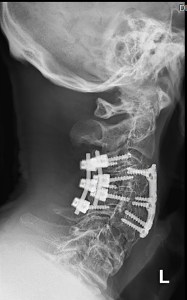

Lots of hardware holding my neck together

This is my neck. It doesn’t look pretty but with this amount of hardware holding it together it’s pretty strong. Quite how it got to be such a mess is a long and convoluted saga but it’s worth telling if only to warn just how badly wrong surgery can go.

“This is to stop the rot” Dr. V. said from behind his surgical mask as I was wheeled into the operating theatre. “Anything else you get back will be a bonus”. The procedure went well with no complications and the rot was stopped but there were no bonuses. Dr. V. had been as good as his word.

Recently I went back to Dr. V. for a checkup on the neck and to asses a potential problem with my lower back which is starting to show signs of degradation below the original war injury that I sustained in the Rhodesian military in 1979 (this is accounted in https://gonexc.com/reflections-on-the-first-half-abridged-and-mostly-expurgated/). It was well treated by the standards of the day but now if you look at the X-ray on the left it’s possible to see where one disc has collapsed below the L4 vertebra and I felt that my gait and balance had suffered as a result. Dr. V. wasn’t so sure and sent me off to see a neurologist for nerve function testing.